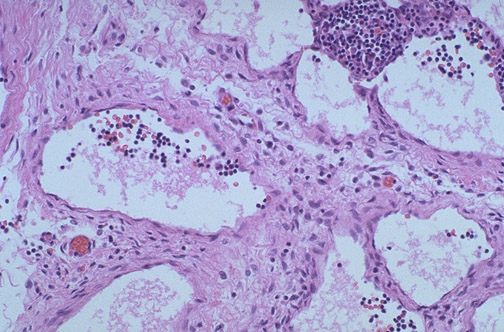

| At high magnification, the histologically benign nature of the lymphangioma is apparent. There are enlarged lymphatic spaces lined by a thin endothelium. However, such lesions tend to be poorly circumscribed and extend widely into surrounding soft tissues, making their surgical removal difficult. |